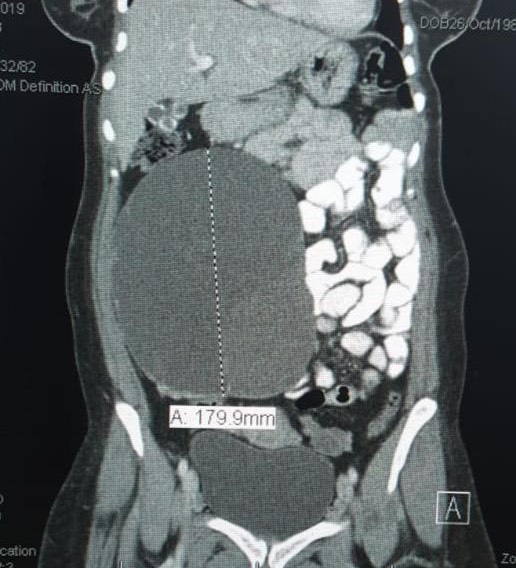

An adnexal mass (mass of the ovary, fallopian tube, or surrounding connective tissues) is a common gynecologic problem. In the United States, it is estimated that there is a 5 to 10% lifetime risk for women undergoing surgery for a suspected ovarian neoplasm. Adnexal masses may be found in females of all ages, from fetuses to older adults, and there are a wide variety of types of masses.  Today, the surgical treatment has become more conservative and less invasive; hence, a laparoscopic approach in the presence of benign cysts has become a golden standard. In the past, patients with previous abdominal surgery were discouraged from undergoing laparoscopic surgery because of its increased risk of bowel injury caused by needle and trocar insertion. Complications occur two times more frequently in patients with previous laparotomy in a study of long series. The potential risk for injury of organs adherent to the abdominal wall during veress needle or trocar insertion as well as the necessity for adhesiolysis and its attendant complications are the two major specific problems constraining surgeons from performing laparoscopic cystectomy/ oophorectomy for patients with previous abdominal surgery. Herein, we report a case of a 32-year-old woman P4 + 2 with history of previous four cesarean section and a following laparotomy for interval sterilization presented to our clinic with abdominal mass, discovered by ultrasound scan, managed by a laparoscopic approach.